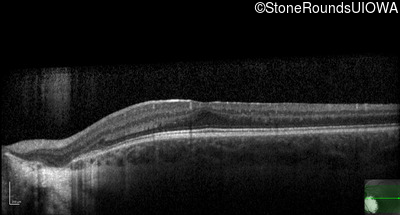

Optical Coherence Tomography - Left - 20/50 +2

Exemplar / OCT Stack